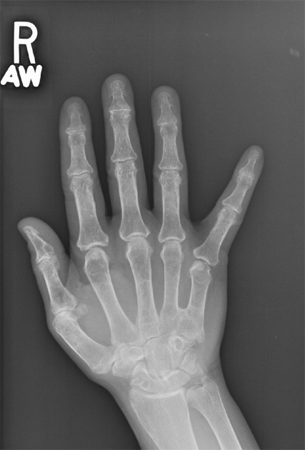

Hands of an adult with Albright's hereditary osteodystrophy showing shortening of the IV metacarpal and distal phalanges, and knuckle dimples in the clenched fists

Wilson LC, Trembath RC. J Med Genet. 1994 Oct;31(10):779-84